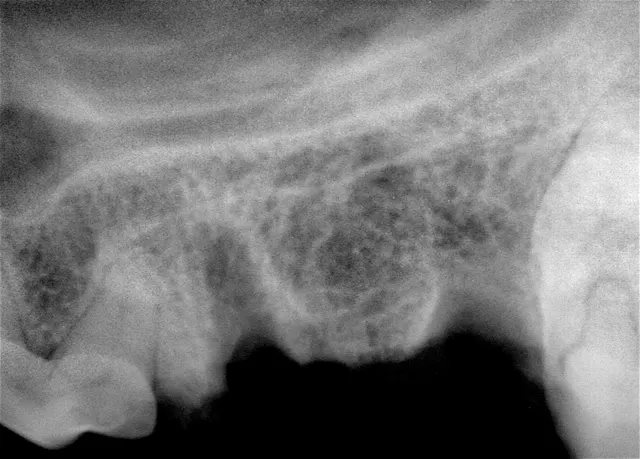

The patient is anesthetized, dental radiographs taken, tooth assessed, and multimodal pain management, including dental nerve block, instituted.

Preoperative radiograph of the maxillary left 4th premolar

The site is radiographed postoperatively (A) and the mucoperiosteal flap is closed using absorbable suture in a simple interrupted pattern (B).